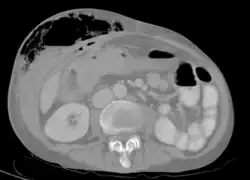

Abdominal CT scan with right colocutaneous fistula and associated subcutaneous pneumatosis